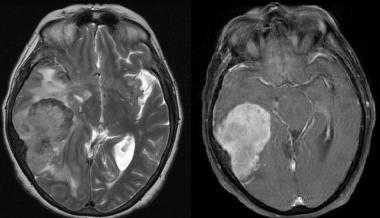

Менингиома теменной области. МР-изображения, полученные с использованием следующих последовательностей: аксиальное Т2-взвешенное, аксиальное Т2-взвешенное, корональное FLAIR -изображение и сагиттальное Т1-изображение. Крупная левосторонняя менингиома выглядит в виде экстрааксиального образования с паттерном «колеса со спицами» и отеком окружающих тканей.